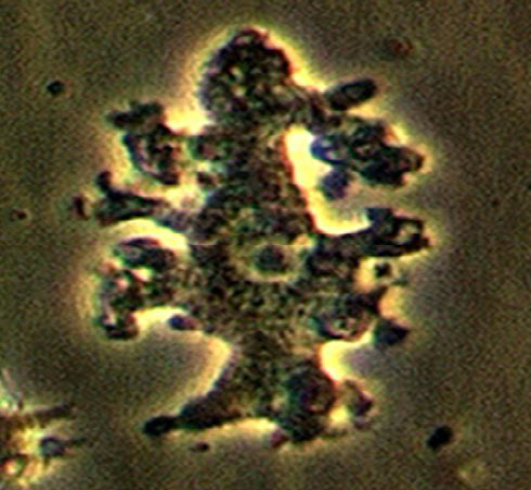

Identify the parasite (Genus, species, and stage).

Mention two characteristic features of this stage.

Mention the direct methods used for diagnosing the neurological form of this disease.

Specify CSF characteristics in case of neurological affection.

Schistosoma mansoni egg

About 140 × 70 µm, colourless, contains mature miracidium

Thin shell with a lateral spine

Confirmation of schistosomal infection by a direct method

Histopathological examination of the nervous tissue

Increased total protein

Presence of eosinophils and antibodies